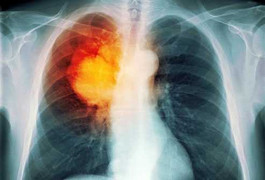

Cứu tinh cho bệnh nhân ung thư phổi: Vừa nội soi phế quản siêu âm vừa sinh thiết

Nội soi phế quản siêu âm giúp vừa quan sát trực tiếp tổn thương và các cơ quan lân cận, vừa thực hiện sinh thiết lấy bệnh phẩm đảm bảo nhanh, hiệu quả, an toàn.

Ung thư phổi là căn bệnh nguy hiểm có tỷ lệ tử vong cao nhất trong các loại bệnh ung thư; theo các nhà khoa học và chuyên gia y tế, thuốc lá là nguyên nhân hàng đầu gây nên căn bệnh đáng sợ này.